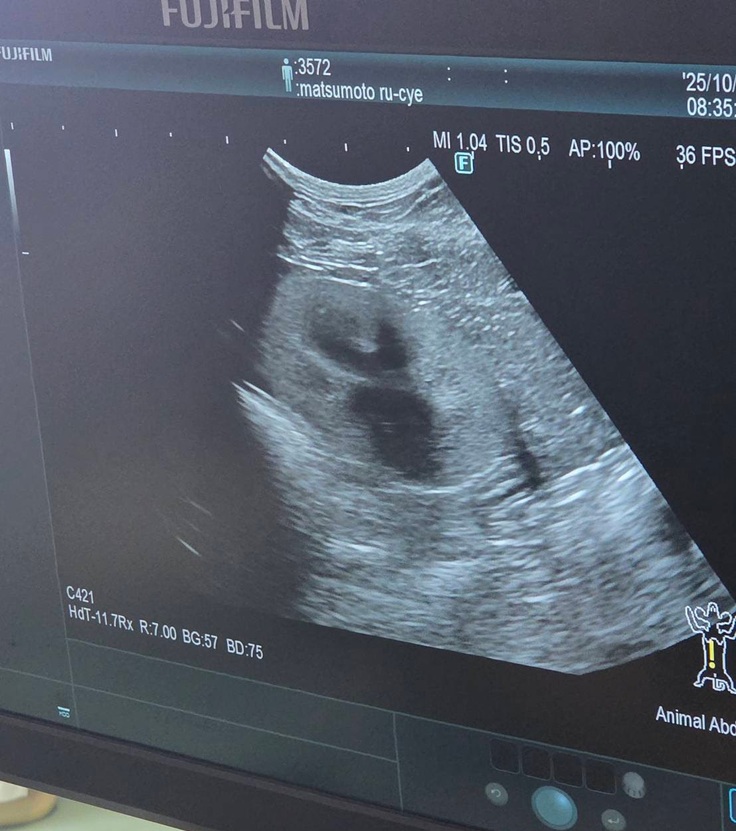

血液検査の写真は撮れなかったのですが、エコー検査では

↓腎臓転移なし

↓肝臓転移なし

↓膀胱転移なし

↓反対側の腎臓も転移なし